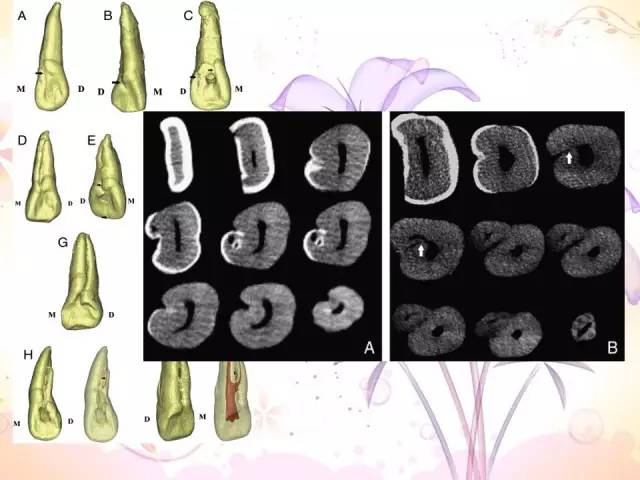

畸形根面沟

上颌侧切牙畸形根面沟2例

左上颌中切牙畸形根面沟并发双根管1例

意向性牙再植术治疗上颌侧切牙畸形舌侧沟1例